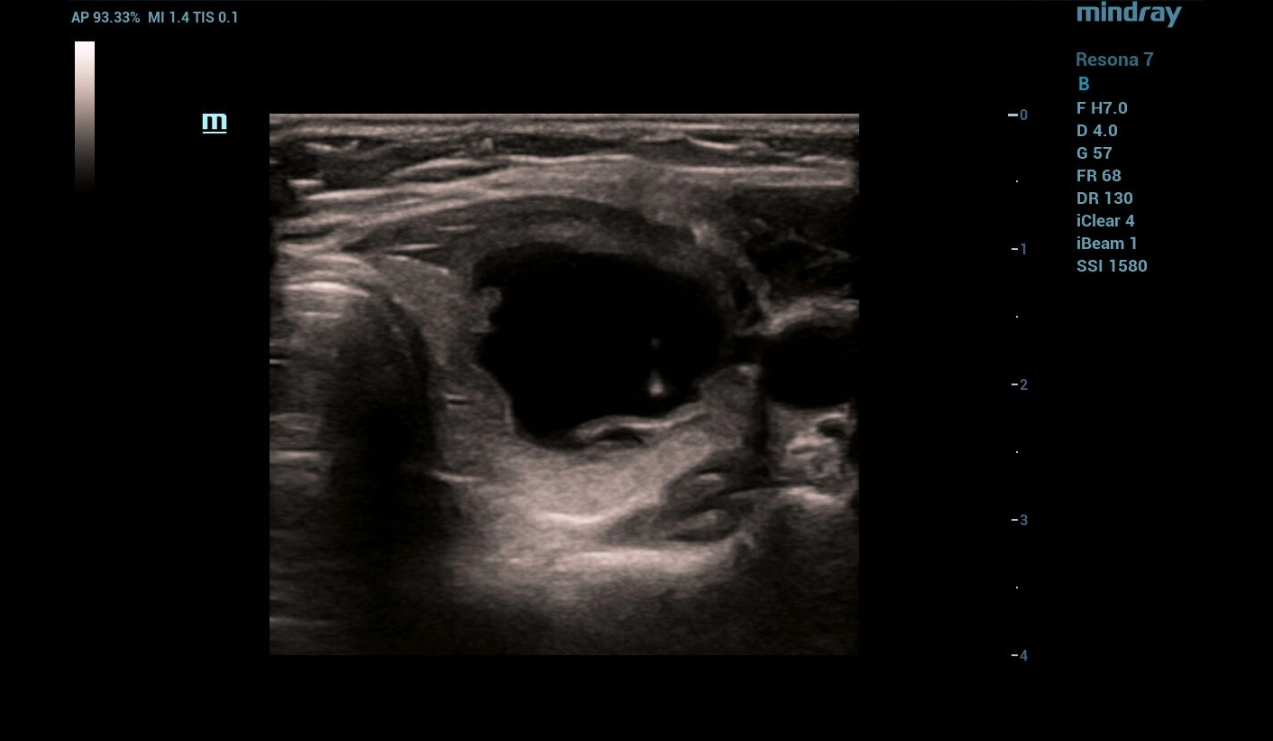

Fine-needle aspiration (FNA) biopsy followed by sclerotherapy with ethanol under ultrasound guidance

Fine-needle aspiration (FNA) biopsy was performed under ultrasound navigation with aspiration of 8.5 ml of clear cystic contents (Fig. 4,5,6) followed by injection of 2.5 ml of sclerosant in the form of 95% alcohol with exposure for 4 minutes (Fig. 7). When sclerosant is injected into the cystic mass cavity in B - mode, the appearance of a hyperechogenic component followed by a decrease in visualization of the needle tip is determined.

Figure 4: FNA of a focal thyroid mass under ultrasound navigation

Figure 5. Aspiration of the contents of a cystic growth of the thyroid under ultrasound navigation

Figure 6. Complete evacuation of cystic contents under ultrasound navigation